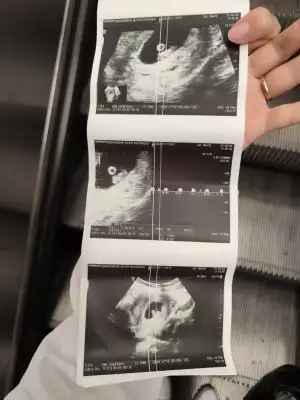

Gözünüz aydın :) karnınızdan mı duyuldu?6+4 keseyi ve kalp atışlarını gördüm Allah herkese bu duyguyu yaşatsın inşallah![]()

Kalp atışı düşük olsa söylerdi doktor canım icini ferah tutKizlar bugun tam 7 haftalik oldum, randevuden ciktim simdi devlete gittigim icin sadece gerekli kisa bir kac bisey soyledi, saglikli kalp atimi var 11. Haftada ikili teste cagirdi. Ama cihazdanmidir bilmem kalp atimi inanilmaz dusuk ve kalp gibide atmiyordu, doktora bagliyorum onemsemediginden bebegin tam kalbindeyken dnlemedi sanirm. Buda usg kagidim, darisi kalp atimi bekleyenlere ins![]()

Kac cm olduğu önemli mi ki benim doktorum gayet yolunda her sey sağlıklı dedi fotolarını verdi benimki vajinal ultrason olduğu için çok net baya olusmus öyle görünce bi garip oldum ben deBurda olcumleri yaziyormu kac cm oldugu